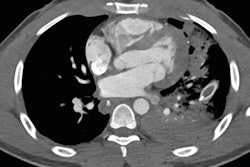

In a Friday presentation, Dr. Savvas Nicolaou from Vancouver General Hospital in Canada discussed the value of CT as a first-line imaging modality for patients presenting in the emergency room with penetrating trauma, such as from gunshot wounds. CT appears to be taking over from x-ray as the initial modality to be used in these cases, and Dr. Nicolaou discussed three signs on CT angiography that can indicate a patient needs urgent evaluation. Find out what they are by clicking here.